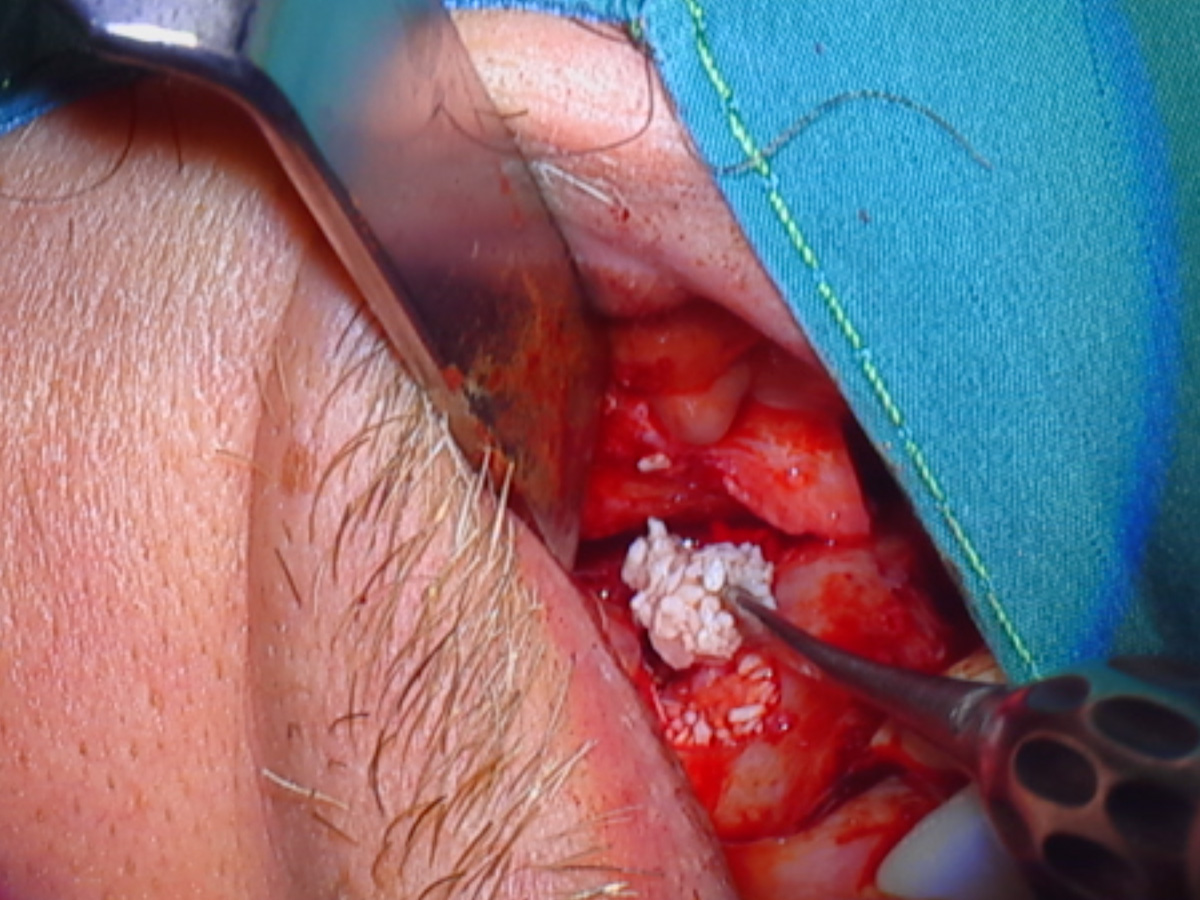

Abbildung 3

Sinusbodenaugementation mit xenogenem Material (Apatos Mix; 10 % Eigenknochen aus Zugangspräparation beigemischt).